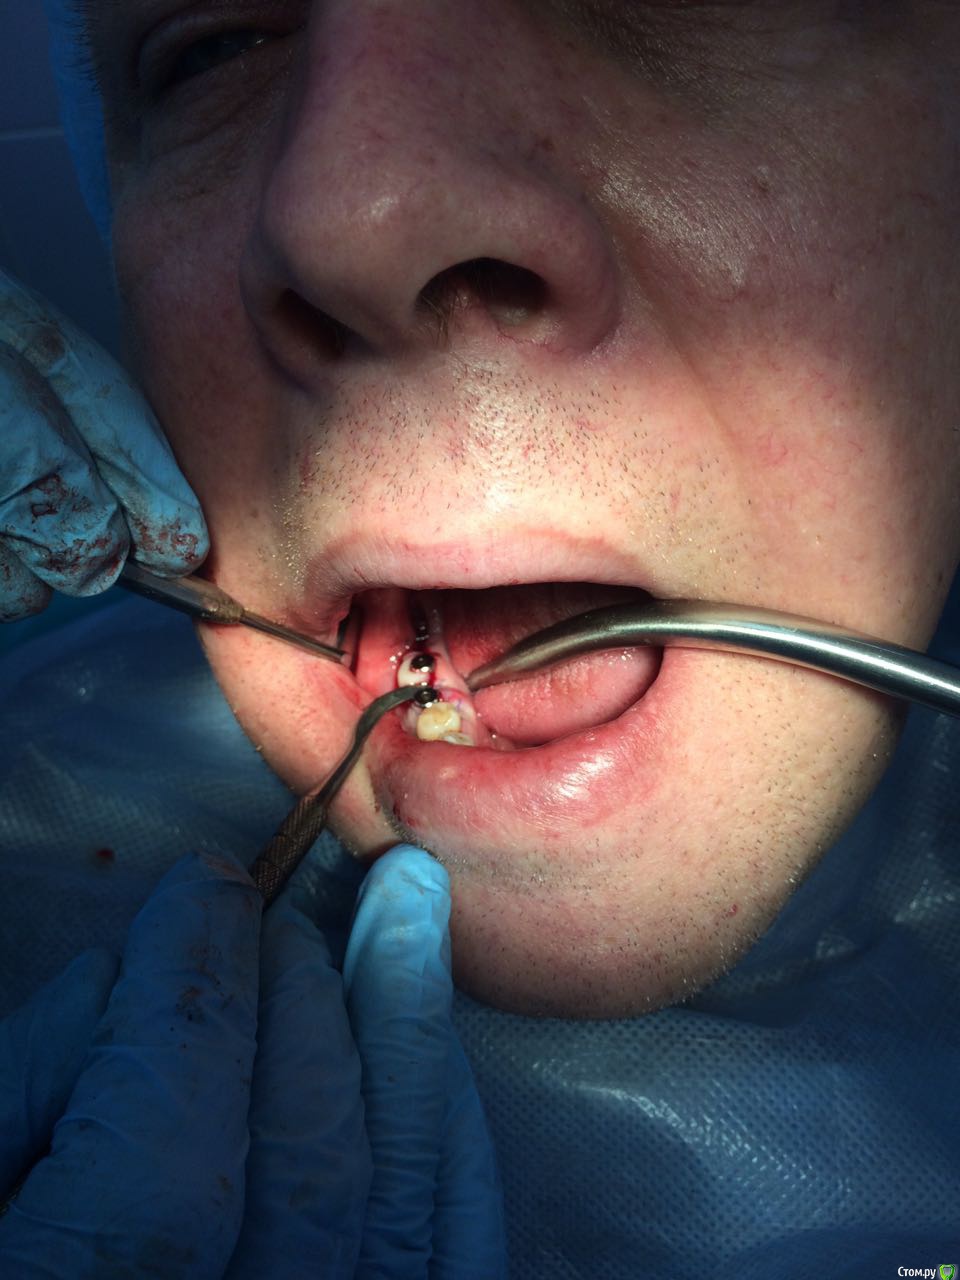

Пациент с жалобами на отсутствие 47 разрушение 46,48. После совещания с ортопедом и терапевтом принято решение удалять 46,48 и устанавливать импланты в позицию 46,47. post-48560-0-74269200-1490419709_thumb.jpgpost-48560-0-43642200-1490419772_thumb.jpgПрисутствует парадонтоз, лечение у пародонтолога прошел заранее. Решено было 46 ставить одномоментно, с графтом и мембранкой, 47 по стандартному протоколу, импланты alpha bio aic 4,2*12, 4,2*10 соответственно. post-48560-0-27512000-1490420040_thumb.jpgpost-48560-0-53003700-1490420066_thumb.jpg Сначала удалил, атравматично с распилом по бифуркации.post-48560-0-43340000-1490420143_thumb.jpgpost-48560-0-35881400-1490420170_thumb.jpgРаскрылся над 47, подготовил ложе, пины параллельности. Здесь вопрос, думаю зря широко отслоился и затронул 46?post-48560-0-32979400-1490420293_thumb.jpgpost-48560-0-94312700-1490420324_thumb.jpgустановка имплантов с фдм, графт в лунки 46 апатос, мембрана Эва. Снять не получилось. Нить моно 5-0. Тут опять вопрос фдм нужно было ставить шире? Но опять же импланты заглубил немного...post-48560-0-50977700-1490420493_thumb.jpg и контрольный. Конструктивная критика приветствуется)))

Фото надо обрезать. У Вас вестибулярный дефект одномоментно с графтом у 46 -лучше законсервировать лунку. 47 также дефицит тканей вестибулярно-сст на узкий фдм. Это какой-то новый альфабио? Я бы не оставлял такой формирователь на весь срок интеграции. На 47 ,судя по всему,фдм не сел,уступ мешает.